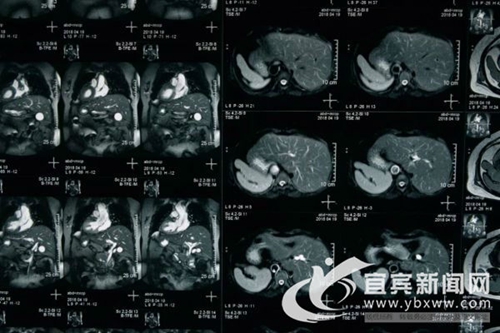

从检查影像上见反向的器官(王铁松 摄)

“镜面人” 是一种罕见的先天性畸形,即全内脏反位,这是一种极为少见的人体内脏解剖变异,指心、肺、横膈、肝、脾、胃、肠等全部内脏的位置呈180度反位。就像是正常人照镜子,位置与常人相反,医学上称为“镜面人”,这在人群中发生的几率仅百万分之一。这种畸形通常不影响人的健康,但一旦患病就会给治疗特别是手术治疗造成巨大障碍。

宜宾县40岁的方女士被诊断为胆囊结石、胆总管多发结石,但和常人不一样的是:她的五脏六腑全都反着长。